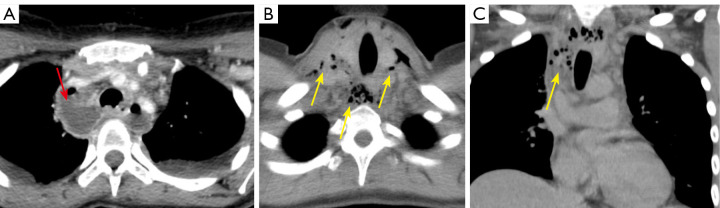

Abstract Image